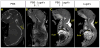

Background: Microcomputed tomography (micro-CT) has been used extensively in research to generate high-resolution 3D images of calcified tissues in small animals nondestructively. It has been especially useful for the characterization of skeletal mutations but limited in its utility for the analysis of soft tissue such as the cardiovascular system. Visualization of the cardiovascular system has been largely restricted to structures that can be filled with radiopaque intravascular contrast agents in adult animals. Recent ex vivo studies using osmium tetroxide, iodinated contrast agents, inorganic iodine, and phosphotungstic acid have demonstrated the ability to stain soft tissues differentially, allowing for high intertissue contrast in micro-CT images. In the present study, we demonstrate the application of this technology for visualization of cardiovascular structures in developing mouse embryos using Lugol solution (aqueous potassium iodide plus iodine).

Methods and results: We show the optimization of this method to obtain ex vivo micro-CT images of embryonic and neonatal mice with excellent soft-tissue contrast. We demonstrate the utility of this method to visualize key structures during cardiovascular development at various stages of embryogenesis. Our method benefits from the ease of sample preparation, low toxicity, and low cost. Furthermore, we show how multiple cardiac defects can be demonstrated by micro-CT in a single specimen with a known genetic lesion. Indeed, a previously undescribed cardiac venous abnormality is revealed in a PlexinD1 mutant mouse.

Conclusions: Micro-CT of iodine-stained tissue is a valuable technique for the characterization of cardiovascular development and defects in mouse models of congenital heart disease.